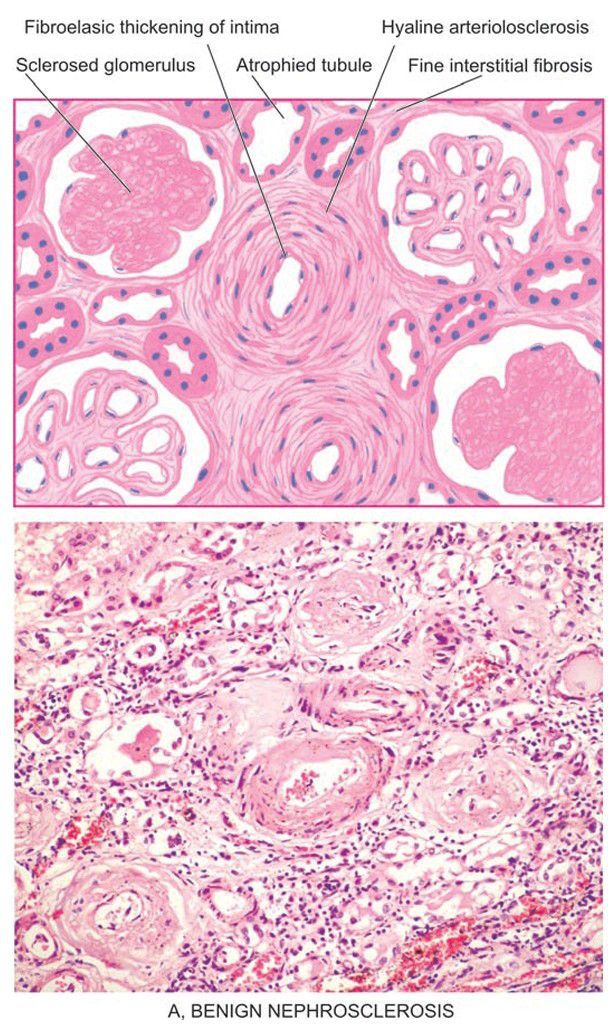

Microscopic changes in kidney in hypertension

. Benign nephrosclerosis. The vascular changes are hyaline arteriolosclerosis and intimal thickening of small blood vessels in the glomerular tuft. The parenchymal changes include sclerosed glomeruli, tubular atrophy and fine interstitial fibrosis.